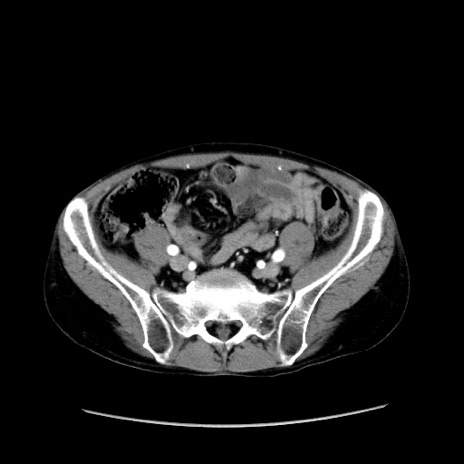

症例37(横断像)

【症例】40歳代 男性

【主訴】腹痛

【現病歴】4時間ほど前に電車に乗車中に臍部上より腹痛出現。徐々に増悪し起立困難となり、救急外来受診。生ものは数日食べていない。今朝お雑煮を食べた。

【身体所見】BT 36.8℃、BP 117/84mmHg、HR 91/min、SpO2 97%、苦悶様、腹部:臍上部広範囲圧痛あり、反跳痛±

【データ】WBC 8100、CRP 0.03